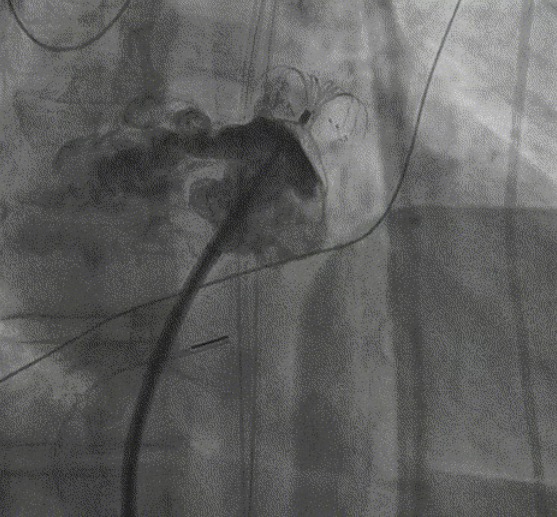

造影封堵成功